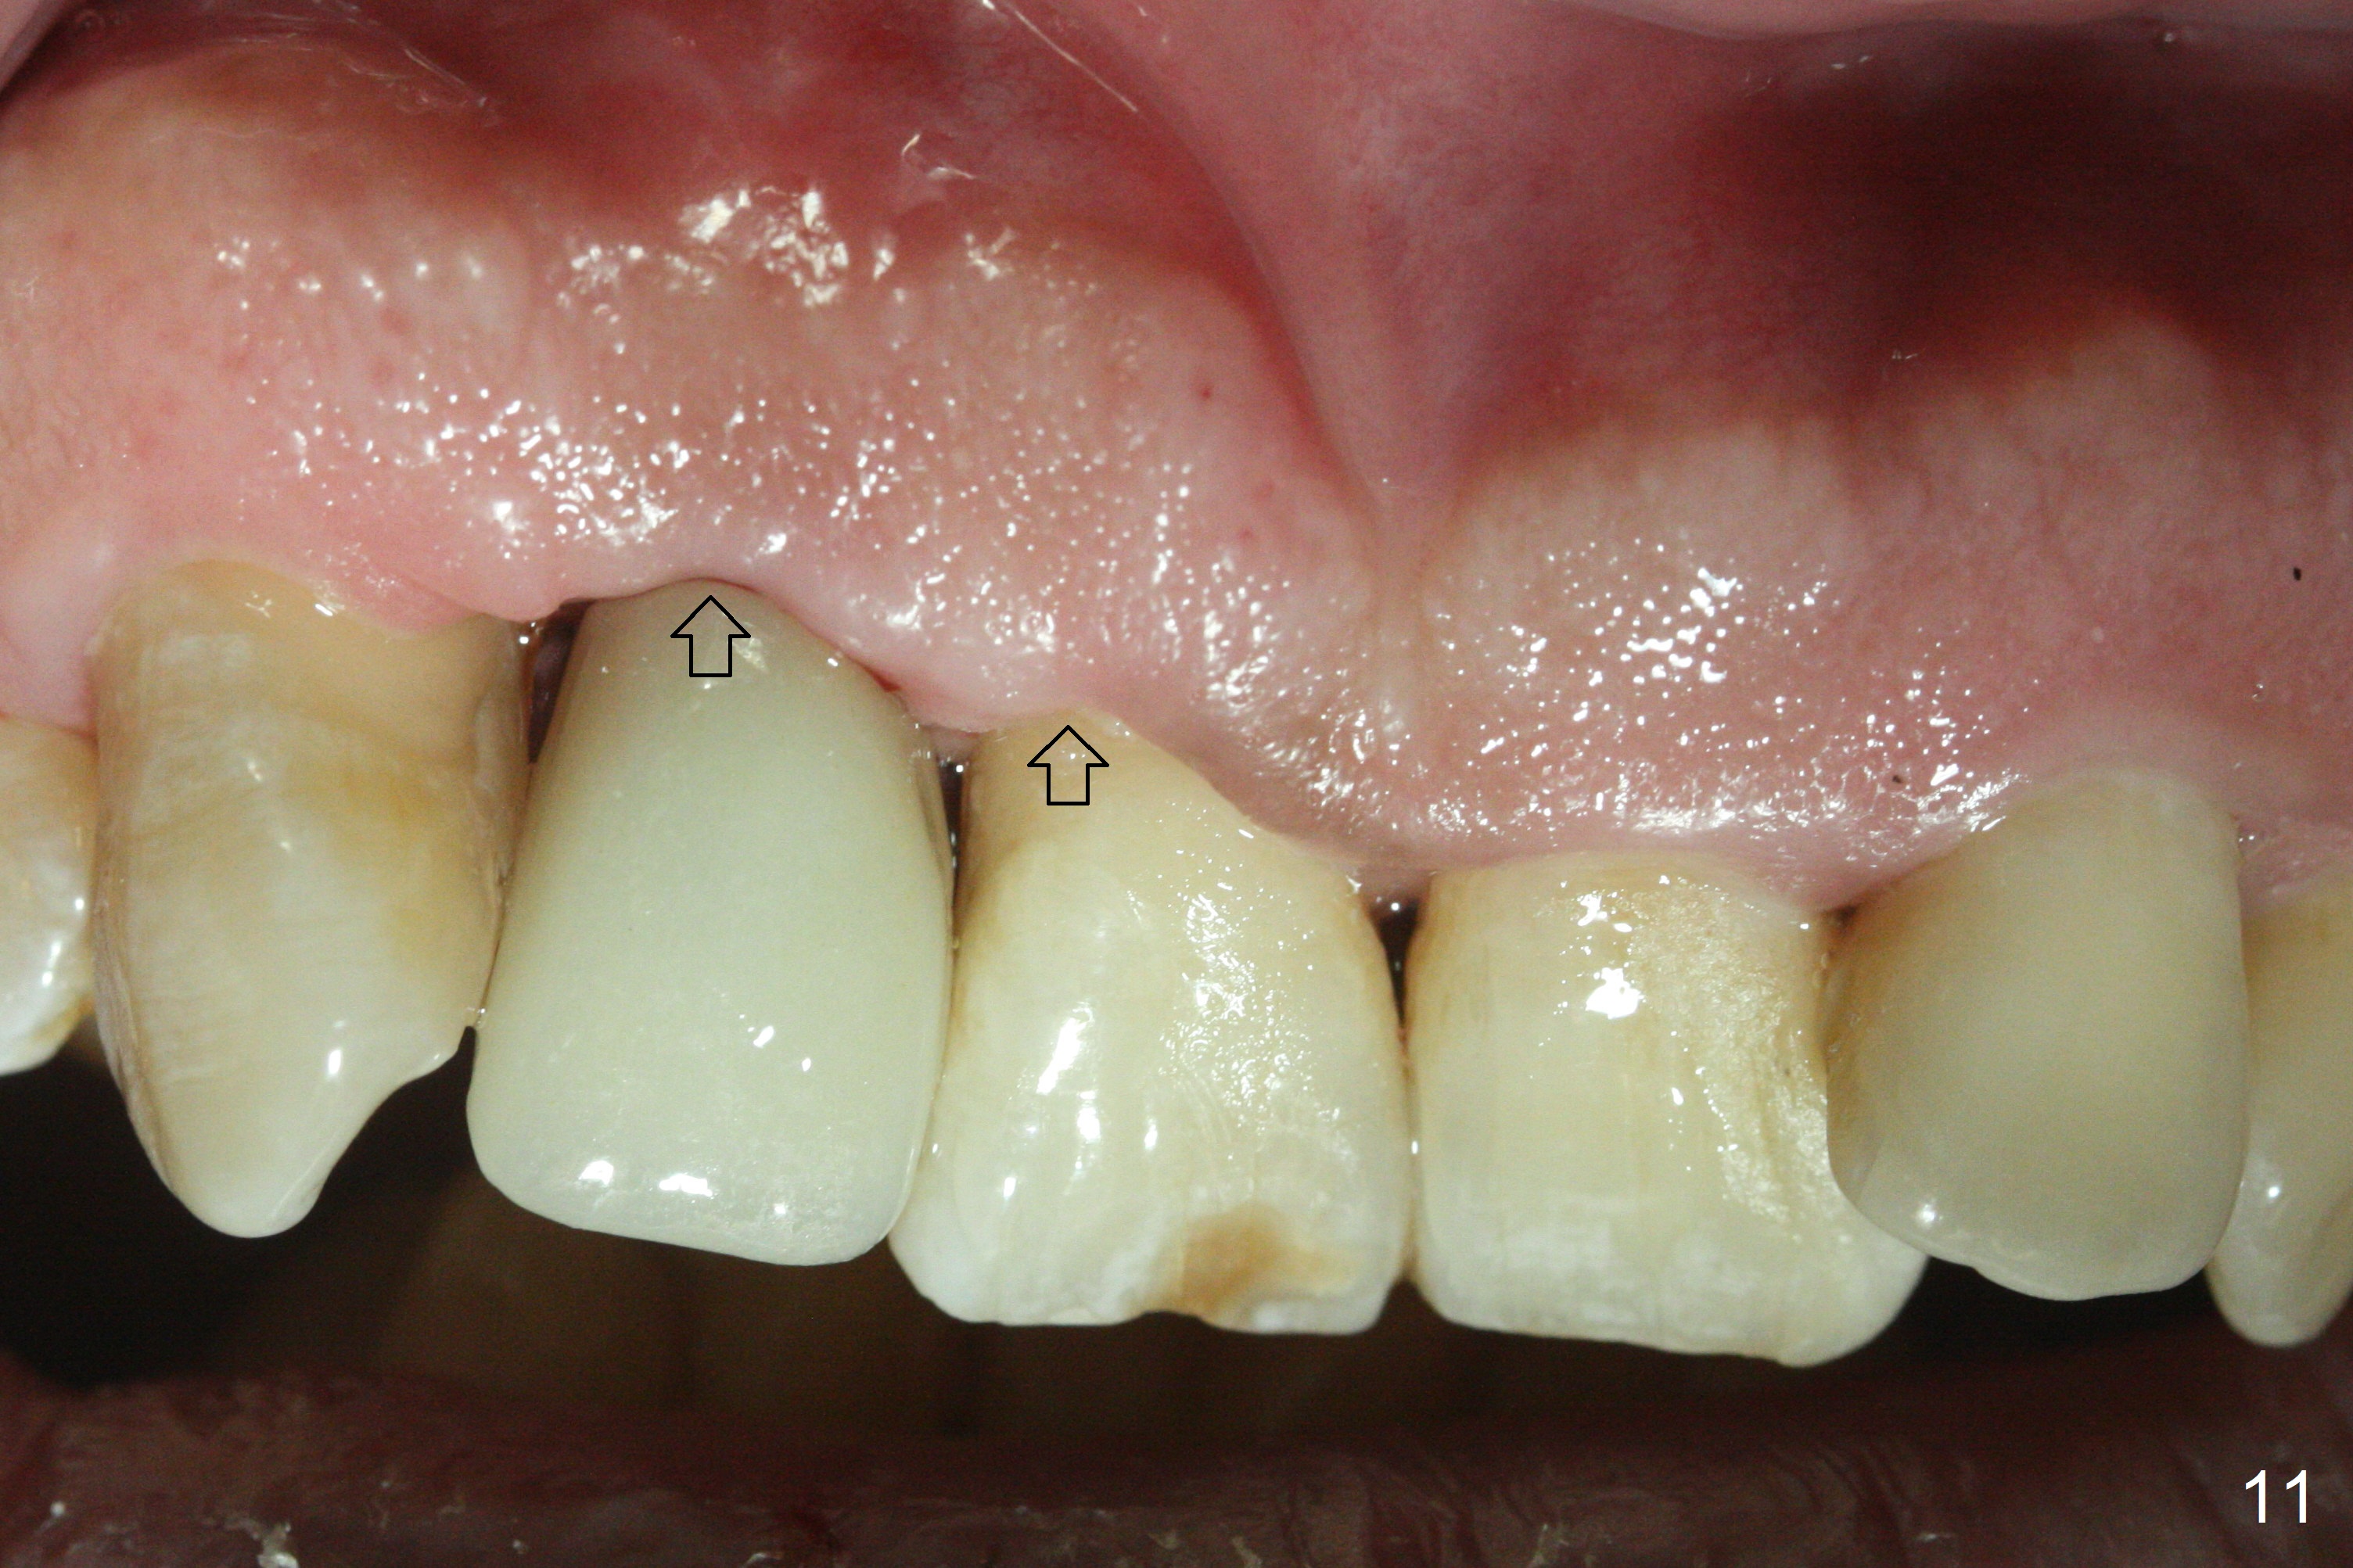

Sixteen days postop, the patient is doing fine, although the labial fistula has not disappeared (Fig.8 <). The detached distolabial papilla is healing (Fig.9 *) with mild bone graft exposure (^). The lacerated distopalatal papilla is also healing (Fig.10 *). These complications are related to flap surgery. The apical portion of the socket appears to have reduced 4 months postop (Fig.14). When the definitive restoration is delivered 5 months postop, there is gingival recession, including the distal of #8 (Fig.11 arrows, which is expected to improve over time) due to flap surgery. The labial plate collapse is minimal (Fig.12 *), while the palatal laceration (Fig.10) has healed (Fig.13). When the patient returns 1.5 years post cementation, there is increased bone density next to the coronal portion of the implant, equivalent to the bone graft (Fig.15 *). The fistula is absent (Fig.16). The crestal bone loss remains 2.5 years post cementation (Fig.17 *), although there is no sign of periimplantitis (magnification). Oral hygiene is poor. There is no change in the soft (gingival recession; data not shown) or hard tissues 3 years 8 months post cementation (Fig.18).